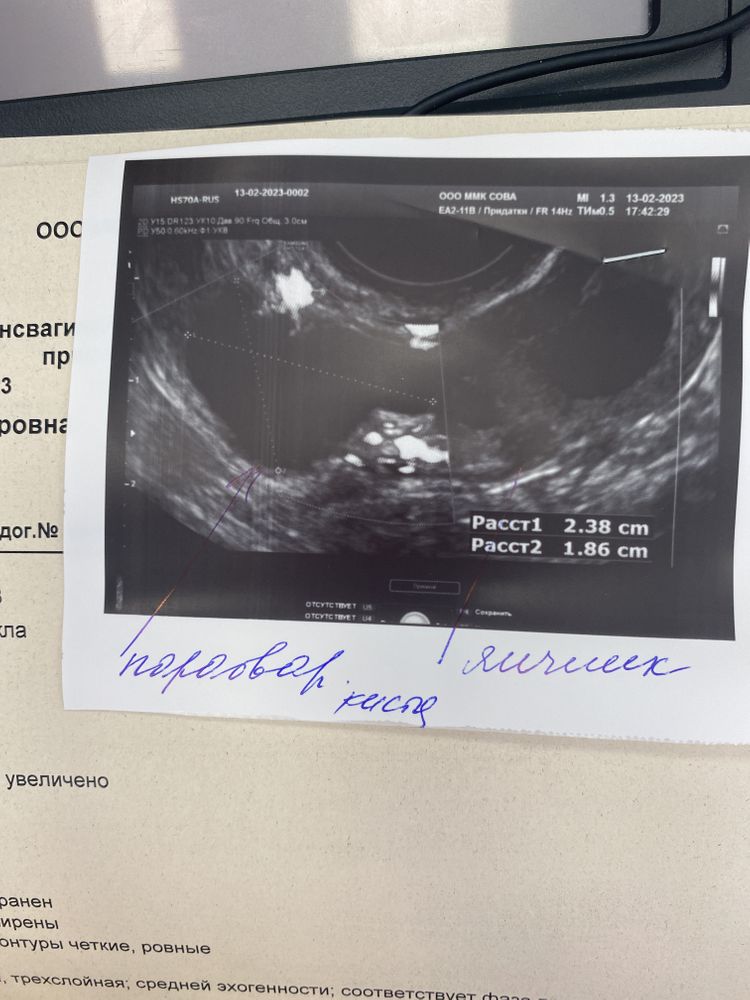

В этом цикле была супер овуляция, по узи было 2 доминантных фолликула с обоих сторон. ЯБ как никогда было очень много) Но вот из-за того что я сомневалась надо ли планировать в период пока меня лечили аутогемотерапией, метронидазолом и противовоспалительными внутривенными уколами и лонгидазой, мы могли и опоздать. В общем воспалилась моя параовариальная киста. Лечили ее.

Завтра утром иду к своему любимому гинекологу, хочу получить независимое третье мнение о моем воспалении.. все советуют вырезать эту кисту. Иначе она так и будет воспаляться, и может быть угроза внематочной если после воспалений она даст спайки…